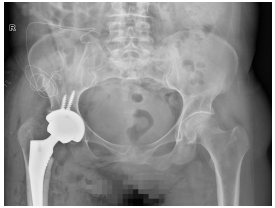

- ·阿坝州人民医院成功实施全髋关节置[2026-04-27]

吴俊一科室:骨科

职称:阿坝州人民医院骨科主任 -